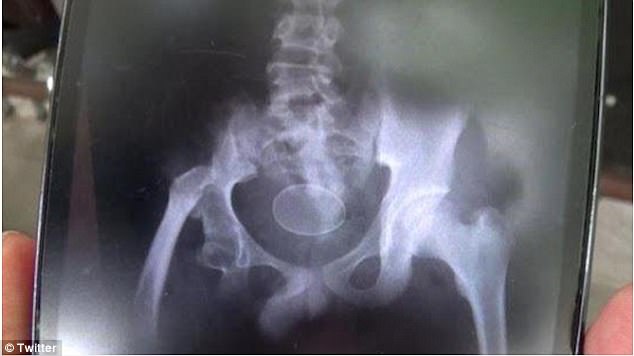

وهذه الحالة التي بدأ أكمل يعاني منها في عام 2016، تأتي على شكل نوبات من الألم، مما اضطر الصبي للذهاب إلى المستشفى عدة مرات. وقد وضع الصبي مؤخراً بيضتين دفعة واحدة على مرأى من الأطباء الذين وصفوا حالته بأنها معجزة.

وقال والد الصبي معلقاً على حالة ابنه: "لقد وضع ابني 18 بيضة خلال عامين، وفي المرة الأخيرة وضع بيضتين دفعة واحدة".

ويقول الأطباء إنه من المستحيل أن يتشكل البيض داخل جسم الإنسان، وشكك متحدث باسم المستشفى في ما يحدث وقال إن الصبي ربما يقوم بإدخال البيض عمداً إلى جسمه.

من جهته نفى والد الصبي ادعاءات الأطباء، وأكد أن البيض يتشكل في جوف الصبي بشكل طبيعي. وقد قام الأطباء بالحجر الصحي على المراهق، لدراسة حالته في مستشفى الشيخ يوسف في ولاية غوا، وفق ما ورد في صحيفة "دايلي ميل" البريطانية.